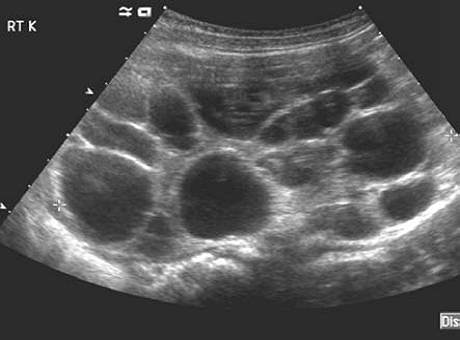

В результаті вся тканину нирки являє собою кісти - мішковидні порожнини різного діаметру з рідким вмістом і сполучнотканинними стінками. Якщо якийсь час ниркова тканина секретуватися сечу, але вона не знаходила виходу, кісти заповнені сечею.

З інструментальних методів найефективнішим вважається УЗД нирок. На моніторі видно множинні анехогенние освіти різного розміру і форми, що містять рідину. У дорослої людини це утворення може бути розміром з волоський горіх, а в стінках кіст сформовані обизвествленние ділянки.

При допплеровском скануванні видно кровотік, який може повністю бути відсутнім, бути обмежений магістральними або сегментарними судинами. Судинний малюнок на поверхні кіст різко збіднений. Необхідне проведення диференціальної діагностики з термінальною фазою гідронефрозу.